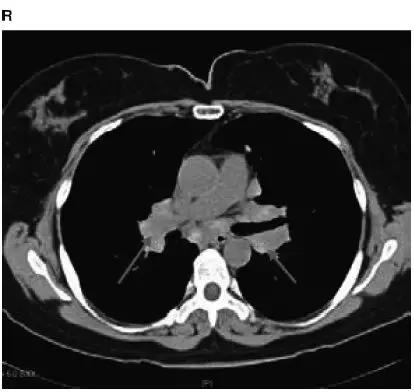

图4-22 Ⅰ期结节病CT:显示肺门和纵隔淋巴结明显肿大(红箭头)